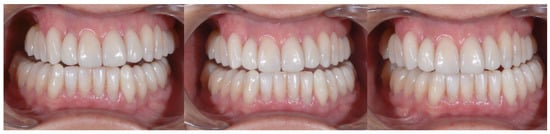

2.3. Outcome Achieved

| Before | After | |

| Disharmonious smile | Yes | No |

| Dyschromia, dysmorphia, abrasions, and erosions of teeth | Yes | No |

| Anterior crowding in the upper arch | Yes | No |

| Anterior crowding in the lower arch | Yes | No |

| Upper transverse discrepancy | Yes | No |

| Presence of buccal corridors or black tunnels | Yes | No |

| Curve of Spee alteration | Yes | No |

| Curve of Wilson alteration | Yes | No |

| Functional movements with altered guides | Yes | No |

| Pain and/or noise ATM | Yes | No |

| Parameter Examined | Clinical Significance | Result Obtained |

| Smile symmetry | Smile symmetry refers to the mirror agreement between the two sides of the mouth but can also consider the bi-pupillary line, the incisal line, and the labial commissure. | YES |

| Horizontal symmetry | It originates from the presence of similar elements placed in a regular sequence, as verified in a dentition with teeth well aligned in the horizontal plane. | YES |

| Vertical symmetry | Recall the same principle as above, referring to the vertical direction. | YES |

| Repeated report | It indicates the division of space into portions that may not be identical in shape and size but arranged to generate a harmonious connection between them. This is what is verified between opposing hemiarches with well-arranged teeth, inspiring a sense of order and balance. | YES |

| Prospective effect | The contour of the buccal surface and the alignment of the inclined planes of the teeth is decisive in generating a correct perspective effect. The different length or strong color difference of even one element can impair the perspective effect and compromise the sense of harmony of the whole. | YES |

| Lip height | Useful distinction in static and dynamic harmony. The average height of the upper vermilion is 7.1 mm in the male and 7.7 mm in the female. The lower vermilion is normally more extensive, about 10 mm on average; these are statistical values, with wide individual variations. | YES |

| Lip line | The height of the upper lip, relative to the upper central incisors, can be classified as low, medium, or high, on the basis of the amount of crown exposure. | YES |

| Smile line | Smile line is a curved line passing through the incisal margin of the upper incisors, parallel to the inner margin of the lower lip. | YES |

| Curvature of the upper lip | With superior convexity, it extends from the center toward the lateral triangular spaces. When rectilinear or worse with inverted convexity, it gives the subject a sad and unattractive expression. | YES |

| Frontal axial alignment | The smooth slope of the long axis of the front elements helps generate a sense of regularity. | YES |

| Tooth alignment in the arch | Recalls the anatomical harmony represented by the correct positioning of teeth in the center of the alveolar ridge. | YES |

| Contact point alignment | In the anterior sectors, the contact points are located near the incisal third and their sequence defines a curvilinear pattern. | YES |

| Color | Color is one of the cardinal elements of dental aesthetic recovery. It must always be evaluated in a much broader context, involving many other periodontal, labial, and skin parameters of the patient. | YES |

| Gingival scalloping | Gingival parabolas are decisive for the aesthetic effect of the frontal group. Orthodontic treatment can contribute to their harmonization. | YES |

| Negative space | A restrained smile enhances the characteristics of the teeth, while an excessive smile imparts an unattractive sense of emptiness. | YES |

| Arch geometry | There are several types of arch form related to individual craniofacial conformation that must be recreated or respected by orthodontic treatment. | YES |

| Buccal corridors o black tunnels | A restrained smile enhances the characteristics of the teeth, while an excessive smile imparts an unattractive sense of emptiness. | YES |

| Fibonacci golden proportion | It evaluates proportions by relating harmony to numerical values. In the dental field, it can find application in the evaluation of various dental and facial morphological parameters. | YES |